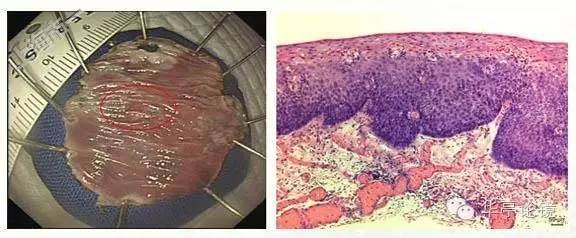

2015年9月30日,我们市一南院消化内镜团队就此病人实施了ESD术,见下图。

完整组织送检,病理:(食道)粘膜表面鳞状上皮低级别上皮内瘤变,局灶高级别上皮内瘤变,水平及垂直切缘均未见病变残留,见下图。

2016年6月7日,病人行ESD术,术顺,以下为完整切除标本。

切除完整标本送检,20160614病理:(食管)粘膜糜烂伴部分区鳞状上皮高级别上皮内瘤变,水平、垂直切缘均未见肿瘤累及。